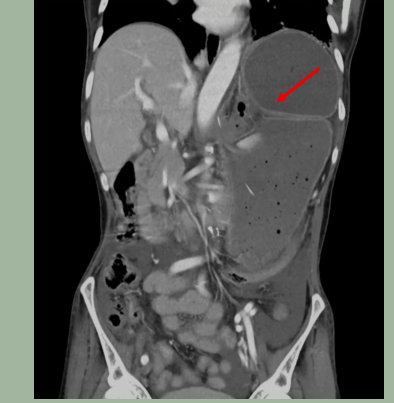

CT影像结果可见胃扭转(箭头所示)

前一阵,59岁的肖姨(化名)进食后突然上腹剧痛、腹胀如鼓、恶心想吐却吐不出来。她到广州医科大学附属第三医院(以下简称“广医三院”)消化内科就诊。本以为是食物不干净吃坏了肚子,没想到CT影像结果出来,医生发现她的胃扭转了270度,胃幽门扭转到膈肌下,十二指肠也被牵拉旋转到了左侧,整个胃被气体和内容物撑得巨大,不仅自身濒临缺血坏死,还使得临近的十二指肠和胰腺受到牵拉和压迫,引发了急性胰腺炎。